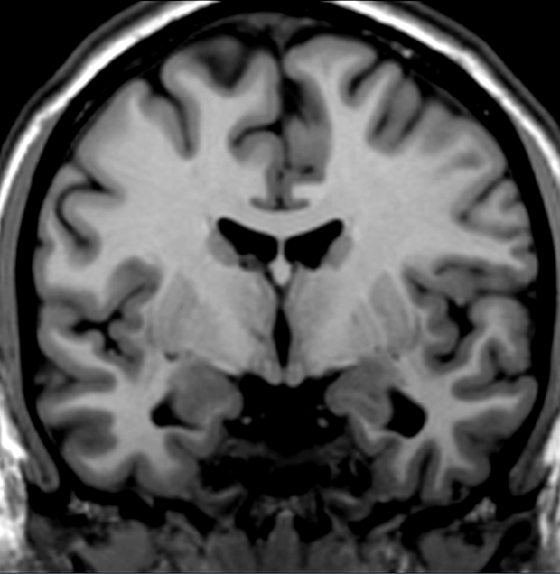

Locate the insular cortex.